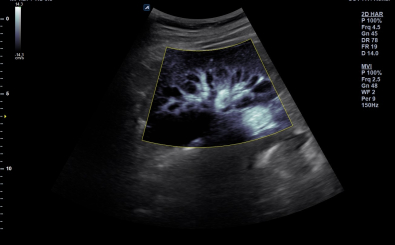

Kidney with MicroView